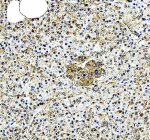

IHC testing of formalin fixed and paraffin embedded human thyroid cancer tissue with recombinant phospho-EIF2A antibody at 1:200 dilution. HIER: steam section in pH6 citrate buffer for 20 min and allow to cool prior to staining.